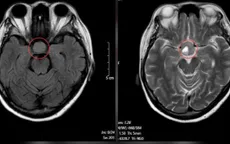

Đau đầu, mờ mắt tưởng cận thị, bé trai 9 tuổi phát hiện mắc u não vị trí nguy hiểm

VTV.vn - Bệnh viện Đa khoa Hùng Vương (Phú Thọ) vừa tiếp nhận 2 trường hợp bệnh nhân đặc biệt đến khám với triệu chứng mờ mắt nhưng phát hiện khối u não lớn.